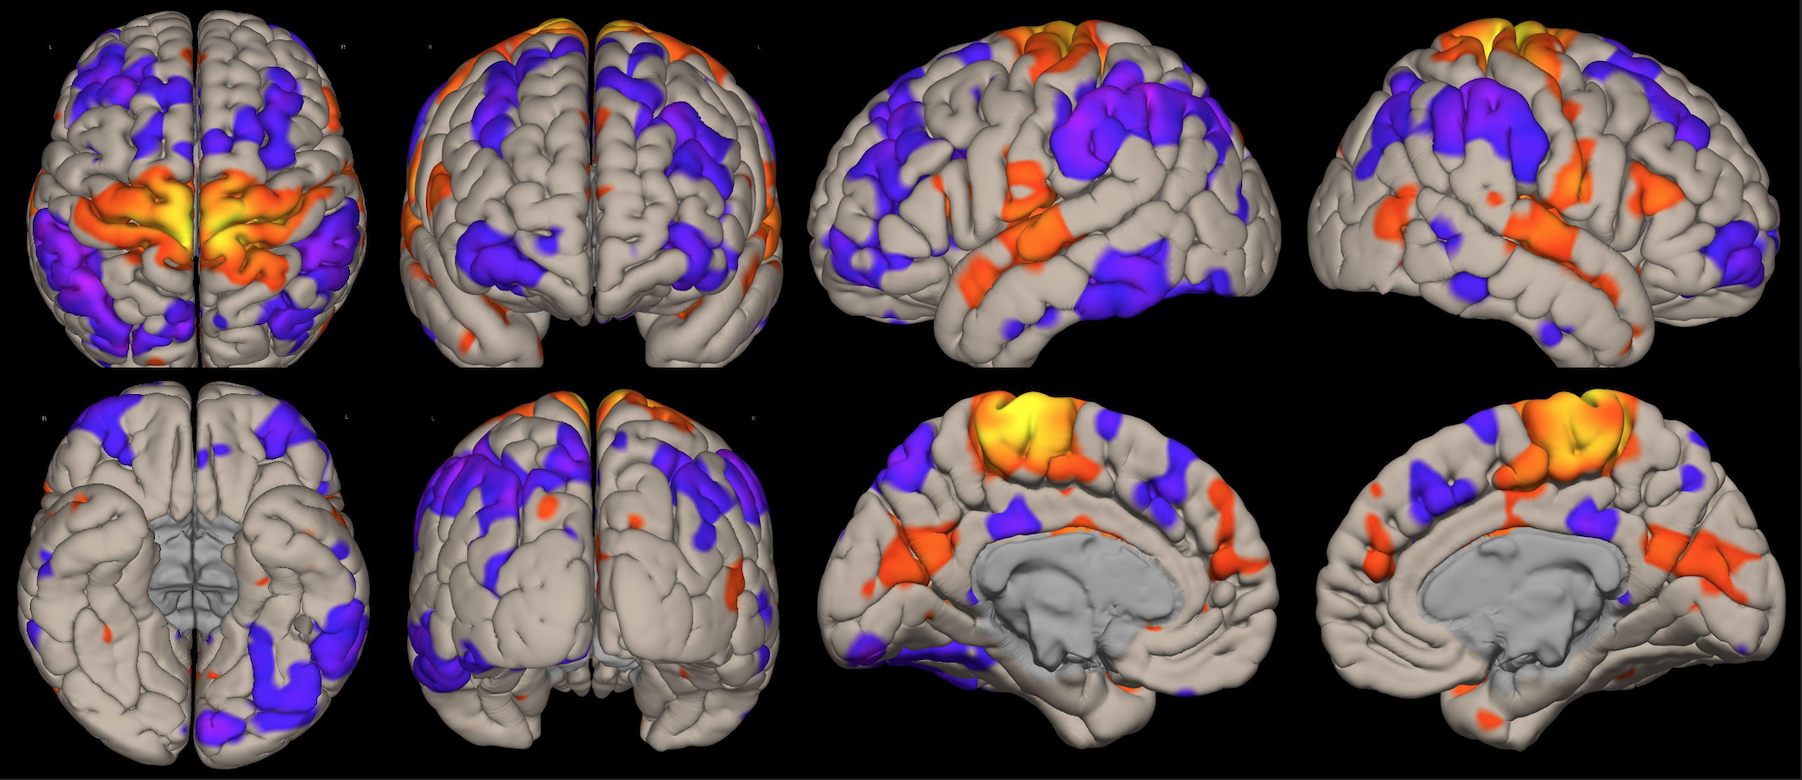

En este estudio, el escaneo se realizó con un resonador de 3 Tesla del servicio de diagnóstico por imágenes de la Clínica Internacional, a un paciente joven, sin comorbilidades ni antecedentes de importancia, el cual estuvo despierto en todo momento y con los ojos cerrados. Además, se le dio instrucciones de completar palabras mentalmente sin emitir sonido alguno o hacer gestos, llegando a identificarse las distintas redes cerebrales detalladas posteriormente.

El estudio fue realizado con secuencia BOLD, con los siguientes parámetros: cortes: 40, factor de distancia: 0%, Field of View: 240 mm, grosor de corte: 4 mm, tamaño de vóxel: 3.8 x 3.8 x 4 mm, TR: 3000 ms, TE: 30 ms, Umbral: 4 y tamaño del paradigma 20.

DISTINTAS CONEXIONES CEREBRALES EN ESTADO DE REPOSO

A pesar de la ausencia actividad física, resulta imposible indicar que no se esté realizando ningún tipo de actividad mental, como recuerdos o el uso de la imaginación. La consecuencia de esto se ve reflejada en los cambios de la actividad neuronal.16 A través de este método de vóxel semilla se ha logrado identificar distintas redes de conectividad funcional descritos a continuación: